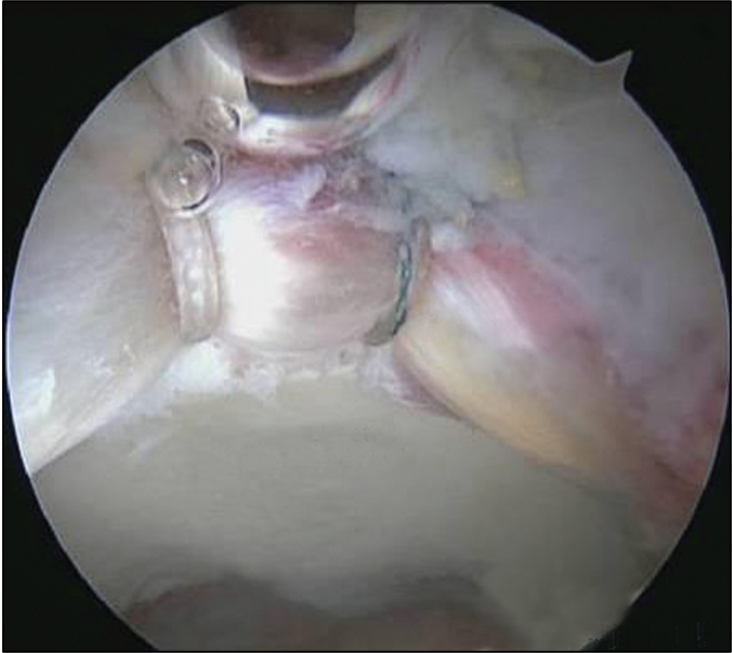

Nelle lesioni del labrum acetabolare è interessata la struttura fibrocartilaginea ad anello fissata al bordo del cotile. Il labrum può essere parzialmente danneggiato o lesionato nella sua intera superficie. Le lesioni sono spesso associate al conflitto femoro-acetabolare, ma possono anche essere isolate (natura traumatica o degenerativa). L'artroscopia d'anca permette la riparazione di tali lesioni fissando il labbro all'osso del cotile mediante il posizionamento di ancorette e punti di tensionamento (fig. 5).

Raggiunta l'articolazione dell'anca si esegue una valutazione in toto dello spazio e delle superfici articolari per verificare l'esatta entità del danno osteocartilagineo, spesso sottostimato dalla valutazione strumentale pre-operatoria e poi si procede all'intervento chirurgico vero e proprio. Per la valutazione e il trattamento della regione periferica (collo del femore) si lavora senza trazione e l'anca viene flessa e ruotata (flessione 45 gradi, rotazione 30 gradi). Diversi strumenti artroscopici potranno essere introdotti nell'articolazione in relazione alle diverse procedure da effettuare (fig. 10).